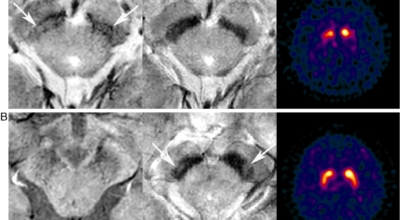

파킨슨병은 도파민 분비 신경 세포의 소실로 발생하는 질환으로 알려져 있는데요 도파민이란 뇌의 신경세포에서 만들어지는 물질로 세포와 세포 간의 신호를 전달하는데 이용되는 신경 전달 물질 중 1개로 이 도파민이 감소함에 따라 파킨슨병이 걸린다고 하는데 이 도파민 세포가 떨어지는 이유는 아직 정확히 알려지지 않았다고 합니다. 일부 파킨슨 환자는 파킨슨병의 가족력이 있는 경우가 있으며 이런 가족들 중 일부에서는 유전자 이상이 발견되기도 해요.